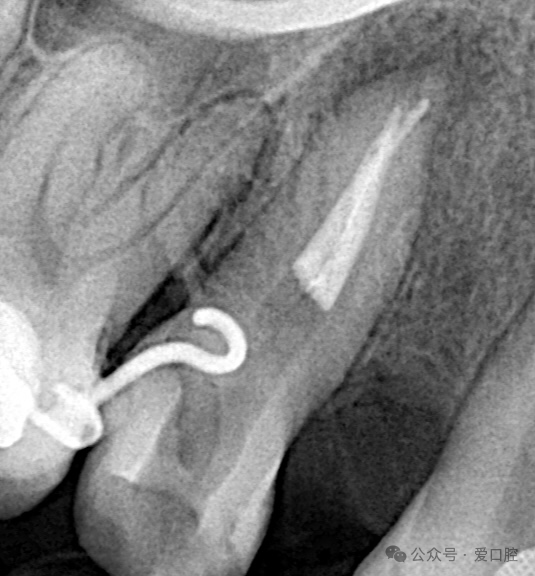

15,安放橡皮障隔离后,显微镜下,开髓,暴露髓腔内牙胶,去除髓腔内牙胶,探查颊侧根管,使用再治疗镍钛锉去除根管上段牙胶,8号k锉,10号k锉疏通至根尖,3%次氯酸钠溶液冲洗,根测长度为19mm,3%次氯酸钠溶液冲洗,探查腭侧根管,发现髓室顶未揭干净,有牙胶残留,揭净髓室顶,去净残留牙胶,疏通腭侧根管至根尖,3%次氯酸钠溶液冲洗,根测长度为19mm,镍钛预备至3504,试尖, 3%次氯酸钠溶液冲洗, Eddy荡洗(20秒3次),蒸馏水冲洗,17%EDTA溶液冲洗,蒸馏水置换,吸干,氢氧化钙封药,玻璃离子暂封。